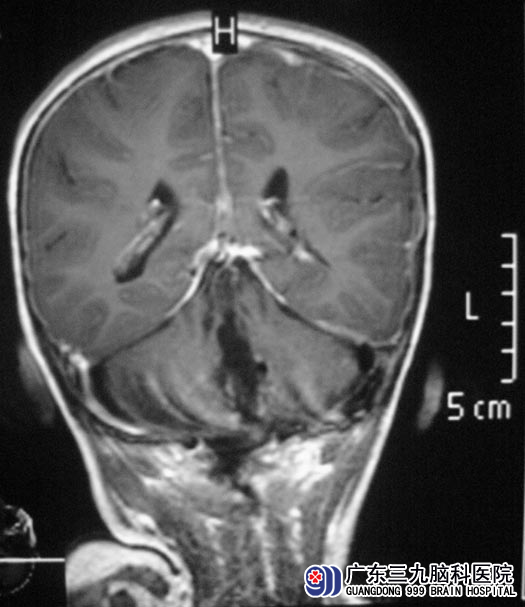

一月前,小宇出现走路不稳,步履蹒跚,易摔倒,家人以为又一次患上手足口病,立即去医院就诊。医生建议行头颅MR检查,结果示;“四脑室占位,大小约4.5cm×4.5cm×5.0cm”,医生告诉他们,手术难度非常大。 http://www.999brain.com/

广东三九脑科医院综合神经外科 鲁明主任了解病史及查阅影像资料后,考虑为髓母细胞瘤合并有梗阻性脑积水。

5月8日,鲁明主任主刀,在全麻下行四脑室内肿瘤切除术。先打开枕大池,释放脑脊液后压力下降,结扎枕窦,见左侧小脑上蚓部肿瘤,呈粉红色,质地不均匀,血供丰富,边界清楚。肿瘤与脑干粘连较重,沿肿瘤与延髓交界处向上分离,行瘤内部分切除,减小肿瘤体积,向上切除部分肿瘤后暴露四脑室顶部,见脑脊液流出,明胶海绵保护。向脑干处继续分离切除肿瘤,见肿瘤与四脑室底部边界清楚,予以仔细分离切除;显微镜下予肿瘤全切,四脑室完整暴露,创面反复止血满意,可见中脑导水管开口,脑脊液引流通畅。手术顺利,术后CT复查,小宇没有出现脑积水等术后并发症。现已康复出院。术后病理证实为:(四脑室)髓母细胞瘤(WHO IV级),后期还需要接受进一步的放化疗。